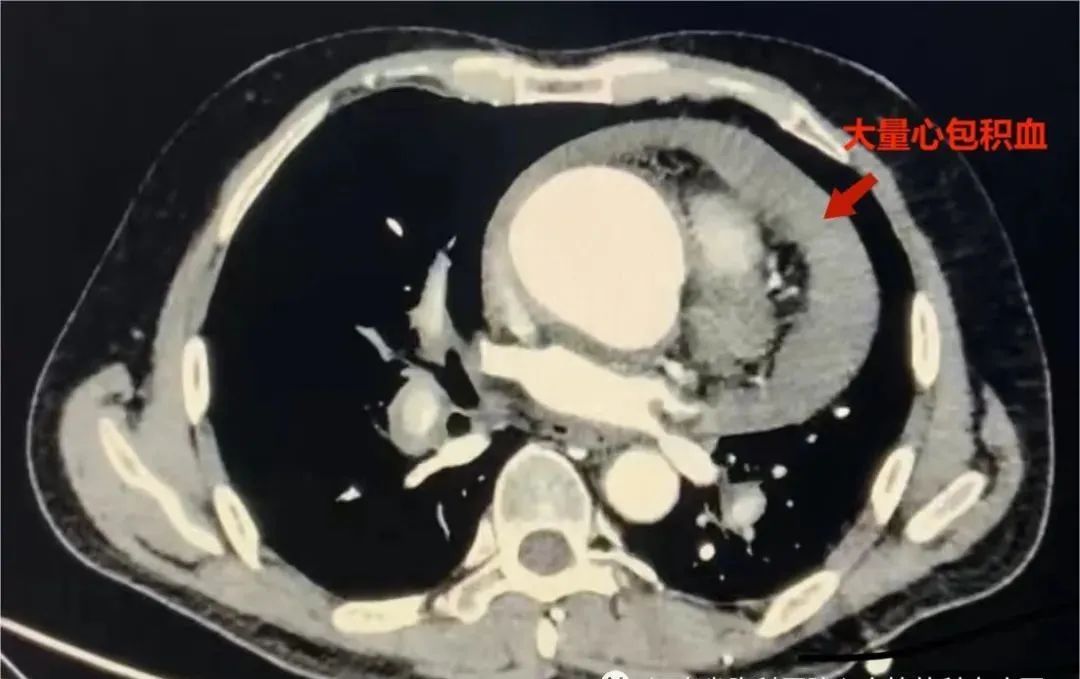

“患者A型主动脉夹层动脉破裂合并急性心包填塞,病情极危,需尽快手术!”肖长波迅速查看资料后,当即确诊病情。

手术开始后,制定股动脉插管,上下并行。张亚飞切股动脉建立动脉插管,同时肖长波开胸,动脉插管成功后,暴露患者心包腔,开一小口后可见暗红色血液涌出,约300ml积血,右房面可见10*6cm2大块血栓块。术中可见主动脉根部瘤改变,直径约65mm,升主动脉外径55mm,主动脉内膜破口位于右冠窦上方2cm,累计2/3周长,升主动脉中段左侧可见外膜破口,可见大量血栓覆盖。

肖长波说,患者长期高血压病,合并全身动脉粥样硬化,同时患有主动脉根部瘤,考虑患者是在主动脉根部瘤的基础上形成A型主动脉夹层,动脉破裂入心包形成急性心包填塞造成血压循环不稳定,急诊行心包穿刺,少量引流出心包积血,循环稍改善后再紧急手术,是李大爷在“命悬一线”的情形下能够活命的最佳治疗方案。